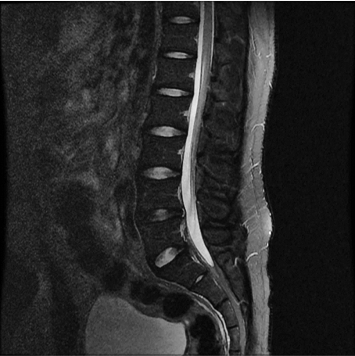

향상된 영상화질

향상된 대조도

노이즈 개선

모든 해부학적 부위 적용가능

384 x 256 (2 NEX)

1:30 minstandard

384 x 256 (4 NEX)

2:59 minIAI (Innovative AI)

384 x 256 (2 NEX)

1:28 minReduced Scan Time

IAI는 AI Deep learning을 통해 기존 장비의 촬영 프로토콜을 최적화합니다.

기존 프로토콜 대비 촬영 시간을 50% 단축시키며, 이미지 퀄리티는 증가합니다.